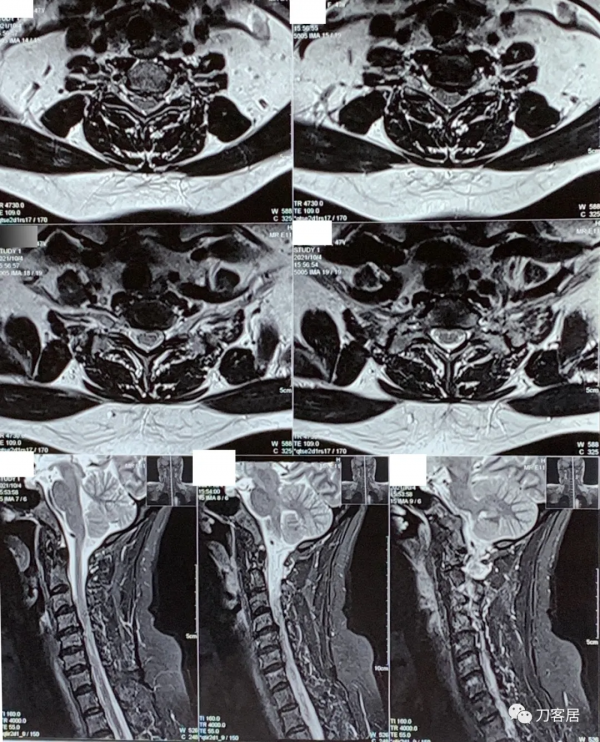

圖6. 20211004胸椎MRI矢狀面T2相,未見明確的胸椎管狹窄。

圖7. 20211004胸椎MRI矢狀面T1相,未見明確的胸椎管狹窄。

圖8. 20211004胸椎MRI矢狀面及橫截面,未見明確的椎管狹窄。

圖9. 20211004頸椎MRI矢狀面T2相及橫截面。提示頸4-5,頸5-6,頸6-7椎間盤突出,椎管狹窄,脊髓訊號改變。

圖10. 20211004頸椎MRI矢狀面T2相及橫截面。提示頸4-5,頸5-6,頸6-7椎間盤突出,椎管狹窄,脊髓訊號改變。

圖11. 20211004頸椎MRI矢狀面T2相,提示頸4-5,頸5-6,頸6-7椎間盤突出,椎管狹窄,脊髓訊號改變。

圖12. 20211004頸椎MRI矢狀面T2相,提示頸4-5,頸5-6椎間盤突出,椎管狹窄,脊髓訊號改變。此兩間隙應該是責任間隙。也應存在頸4-5,頸5-6之間的不穩。

圖13. 20211004頸椎MRI矢狀面T1相,提示頸4-5,頸5-6椎間盤突出,椎管狹窄,脊髓訊號改變。此兩間隙應該是責任間隙。也應存在頸4-5,頸5-6之間的不穩。

圖14. 20211004頸椎MRI矢狀面T1相,提示頸4-5,頸5-6椎間盤突出,椎管狹窄,脊髓訊號改變。此兩間隙應該是責任間隙。也應存在頸4-5,頸5-6之間的不穩。

圖15. 20211004頸椎MRI矢狀面T2相及橫截面。提示頸4-5,頸5-6,頸6-7椎間盤突出,椎管狹窄,脊髓訊號改變。

圖16. 20211004頸椎MRI橫截面。